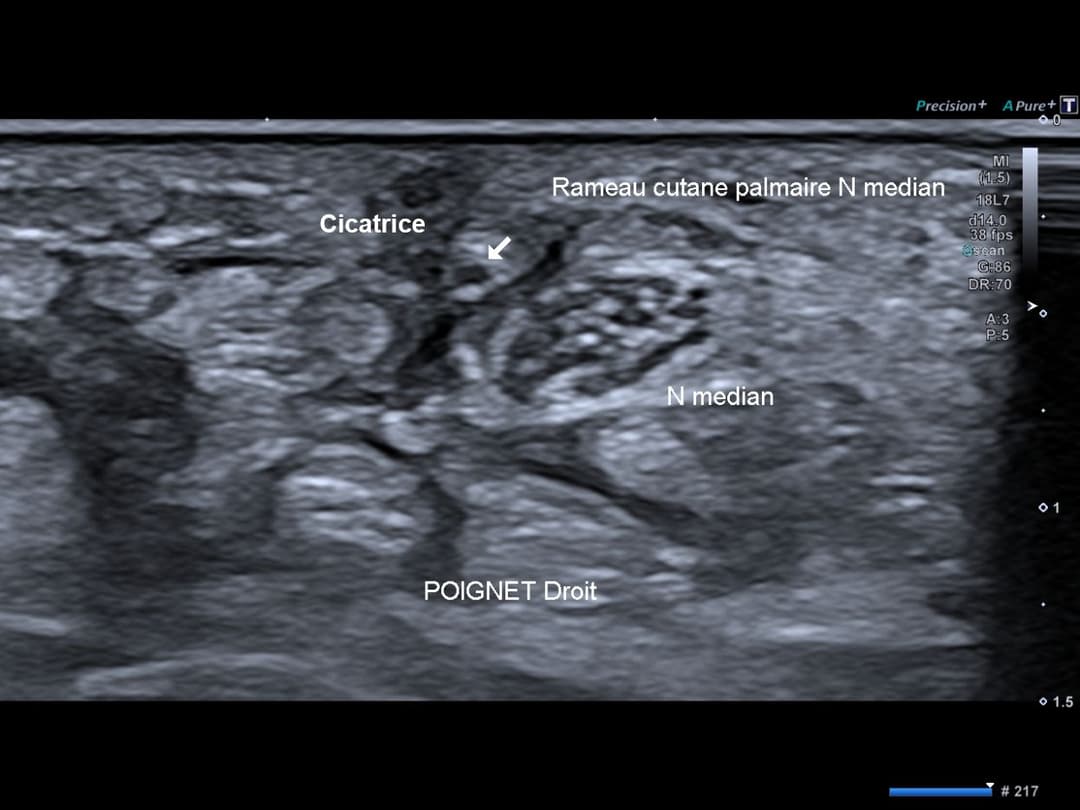

Rameau cutanée palmaire du nerf médian piégé dans la cicatrice cutanée palmaire du tiers distal de l’avant-bras, avec non visibilité de ses fibres efférente traduisant un névrome d’amputation.

Nerf médian de calibre normal et d'échostructure conservé au sein du canal carpien.

Balayage axial du nerf permettant de repérer la perte de sa continuité et son piégeage au sein d'une fibrose sous cicatricielle.

Coupe axiale statique montrant le nerf dans l'environnement cicatriciel, en amont de la lésion